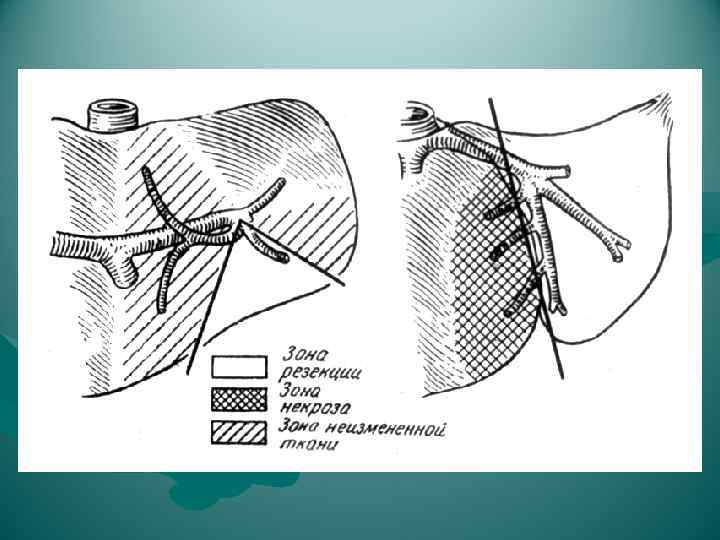

РЕЗЕКЦИЯ ПЕЧЕНИ Атипичные резекции - восточный способ - удаление части органа в пределах здоровых тканей с постепенным, по ходу намеченного пересечения печени, раздавливанием пальцами паренхимы и перевязыванием пальпаторно обнаруженных сосудистых и желчных образований: - краевая - клиновидная - поперечная Основной момент операции - шов печени Преимущество - более экономна с точки зрения количества удаляемой ткани - простота и быстрота Недостаток - возможность опасных неуправляемых кровотечений - возможность некрозов остающихся здоровых участков печени из-за перевязки их сосудов и желчных протоков

РЕЗЕКЦИЯ ПЕЧЕНИ Атипичные резекции - восточный способ - удаление части органа в пределах здоровых тканей с постепенным, по ходу намеченного пересечения печени, раздавливанием пальцами паренхимы и перевязыванием пальпаторно обнаруженных сосудистых и желчных образований: - краевая - клиновидная - поперечная Основной момент операции - шов печени Преимущество - более экономна с точки зрения количества удаляемой ткани - простота и быстрота Недостаток - возможность опасных неуправляемых кровотечений - возможность некрозов остающихся здоровых участков печени из-за перевязки их сосудов и желчных протоков